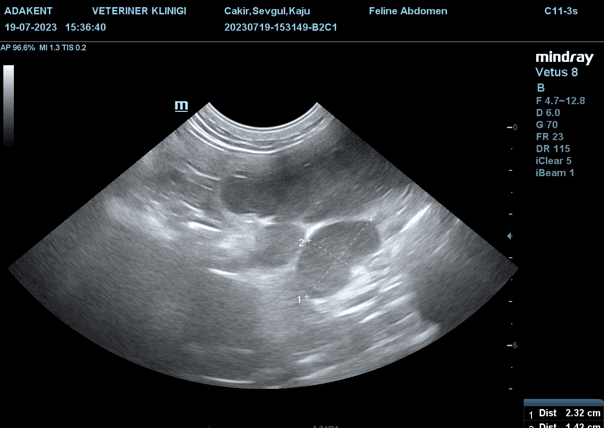

Takip edilen hastamızda da karın palpasyonunda fark edilen şişlik, ultrasonografik görüntüleme ile doğrulanmıştır.